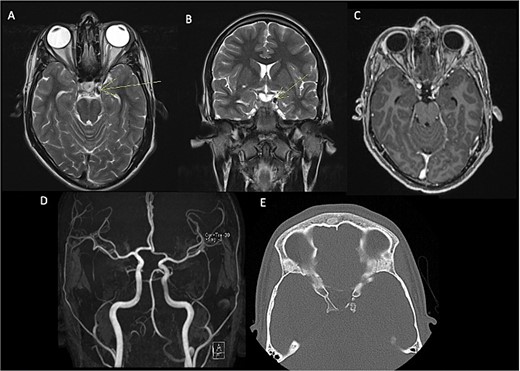

In the initial assessment of painless oculomotor palsy, brain MRI revealed a small, rounded lesion adjacent to the left posterior clinoid process (Fig. 1). Subsequent angiography (MRA) was performed due to suspicion of vascular pathology, confirming a well-defined lesion with low signal intensity in both T1 and T2 sequences. Post-contrast T1-weighted images demonstrated thin peripheral enhancement around the lesion. Aneurysms were ruled out by MRA, and a follow-up head CT scan identified a calcified lesion on the left posterior clinoid process extending into the interclinoid ligament, situated adjacent to the left oculomotor cistern. Additionally, diffuse calcification of the interclinoid ligaments was observed on CT imaging.

Pre-surgical MRI (A–C) showing the presence of a lesion with low signal intensity on T2-weighted sequences (A, B) of 0.7 × 0.6 cm adjacent to anterior clinoid process and tents, concerning the oculomotor left cistern, with peripheral enhancement in post-contrast sequences (C) contacting the left third cranial nerve. No evidence of aneurysms in angiogram MRI (D). Head CT scan (E) with a calcified exophytic lesion concerning the left anterior clinoid.